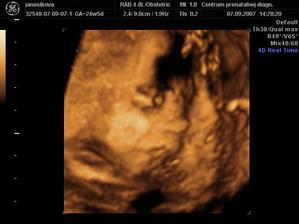

Nasa bambulka...

Tesne pred nasou svadbou sme sa dozvedeli tu najkrajsiu spravicku a to zr cakame babatko, velmi sa tesime🙂